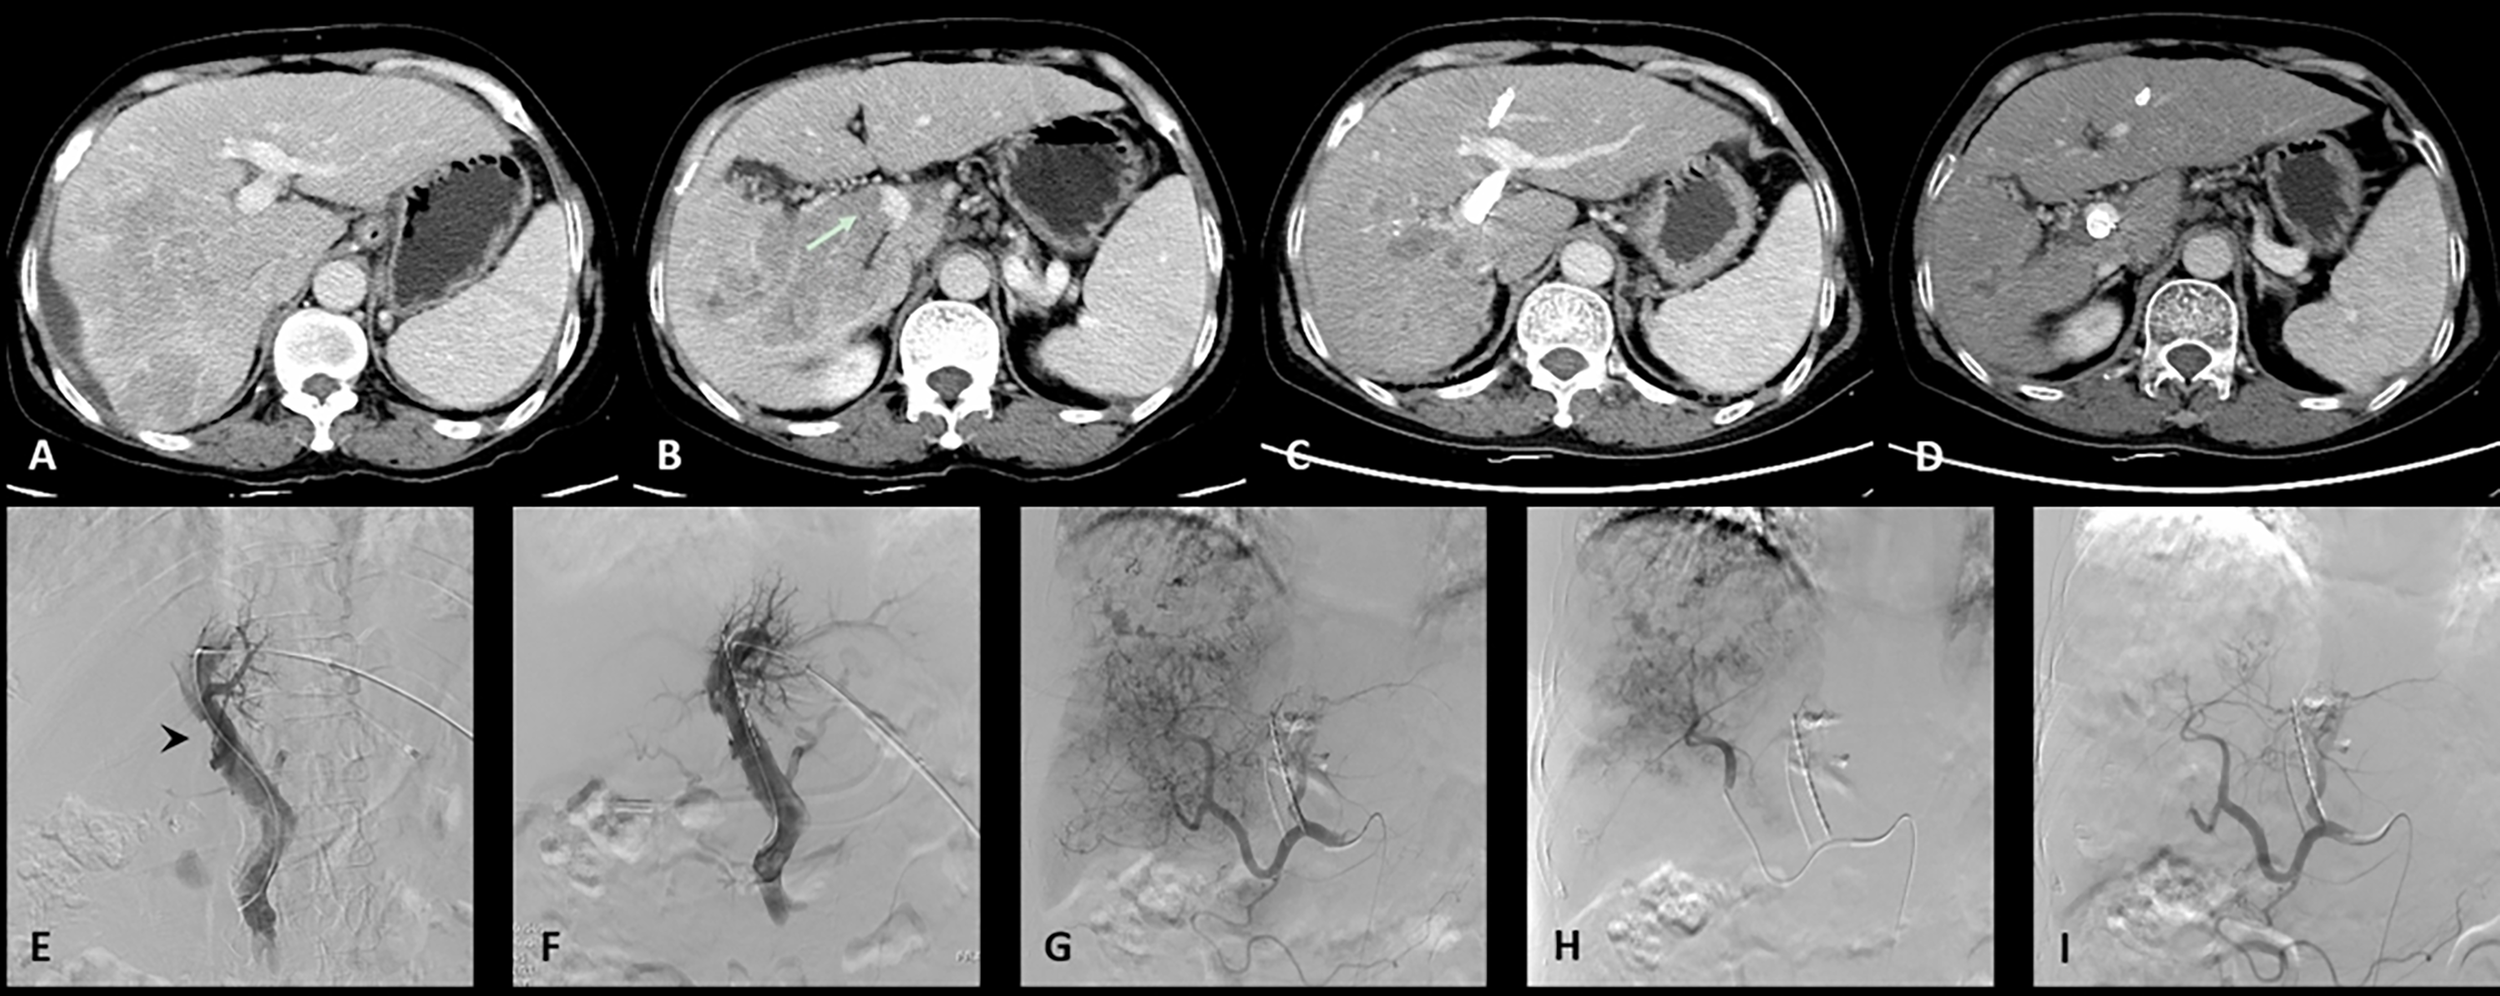

All the patients successfully underwent stent implantation of a radioactive seed into the portal vein followed by TACE treatment. In the C-TACE group (Figure 1), 13 stents were implanted (diameter: 8-14 mm, length: 60–90 mm), 13125I radioactive seeds were used (a total of 204125I seeds, with an average of 16 per strip), and 10.6 ml of lipiodol was used in each case on average. Fifty milligrams of epirubicin were mixed with lipiodol for each case, and 15 boxes of gelatin sponges were used to enhance embolization. In the D-TACE group (Figure 2), 13 stents were implanted (diameter: 8-14 mm, length: 40-94 mm), and 13125 I radioactive seeds were used (a total of 181125I seeds, with an average of 14 per stripe); 18 bottles of DC beads were used; and five boxes of gelatin sponges were used to enhance embolization. Each bottle of DC beads contained a mixture of 40 mg of epirubicin.

Figure 1 One case of the C-TACE group. The patient was a 60 years old female. (A): Preoperative CT images showed a huge tumor in the right lobe of the liver. (B): Tumor thrombus (arrow) was seen in the right branch and main portal vein. (C): After 3 months follow up, the tumor was significantly reduced. (D): The patency of portal vein stent was revealed after 3 months follow up. (E): Filling defect was showed in the main portal vein (arrow head) during venography. (F): Portal vein stent (diameter: 12 mm, length: 60 mm) was implanted and 12 125I radioactive seeds were used. (G): Hepatic artery angiography showed large tumor staining of the right lobe of the liver. (H): Superselective embolization of the tumor artery branches with 50 milligrams of epirubicin mixed with 10 ml lipiodol and 1 box of gelatin sponges was used to enhance embolization. (I): Angiography after embolization, tumor blood supply was significantly reduced.